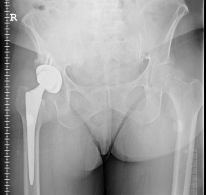

The FDA issued a warning to Zimmer Holdings Inc. regarding its operations for manufacturing and testing of one of its metal on metal hip implants at one of its locations. In a letter written on September 19, 2012, the agency stated that Zimmer failed to comply with federal regulations regarding its production of the Zimmer hip implant, the Trilogy Acetabular System, which was being produced at its Ponce, Puerto Rico plant.

The FDA warning simply adds to the pile in a number of issues regarding Zimmer’s metal on metal hip implant devices. The company is dealing with several Zimmer hip implant lawsuits regarding its Durom Cup, which is a metal socket designed for use in total hip replacement procedures.

Though the Zimmer Durom hip implant device was approved by the FDA in 2006, only a short time passed before it got the attention of orthopedic surgeons and patients, who noticed a loosening of the Zimmer hip implant cup and failure of the device quickly after implantation. The result of this failure was excruciating pain. Artificial hips are said to last around 15 years or so, but this was clearly not the case with many of Zimmer’s metal on metal hip implant products.